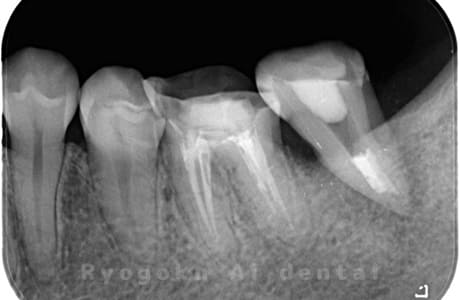

他院で右下の根の治療を行い、セラミックを被せる説明をされていたが、根の治療が終わらないため転院された患者さんです。隣の親知らずの抜歯の必要性と、根の治療を行なっている歯牙の予後が悪いため、移植治療を提案し、右下の親知らずの抜歯と同時に、右下の奥歯(7番)への移植治療を行いました。被せ物を行う必要もなく、順調に経過してます。